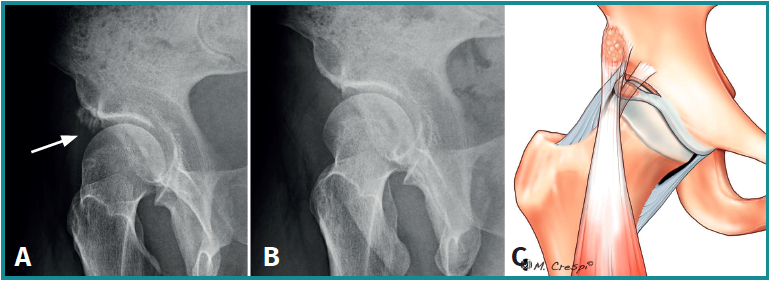

Tipo B: osificación de la porción directa del recto anterior

- Características y morfología radiográfica: en estos casos se visualizará la calcificación cerca del borde superior del acetábulo, generalmente paralela al eje longitudinal del fémur y con 3 posibles variantes: filiforme corto (tipo B1), filiforme largo (tipo B2) y redondeado o difuso (tipo B3)(3)(Figura 6). En los tipos filiformes el aspecto de cola de cometa es característico. Es importante tener en cuenta que existen otras causas de mineralización relacionadas con la porción directa del recto anterior proximal, como las avulsiones de la espina ilíaca anteroinferior o los diferentes tipos de pinzamiento de tipo subespinal.

- Localización y lesiones asociadas: adyacente al borde superior del acetábulo y con deformidades de tipo cam o pincer asociadas en muchos casos.

- Tratamiento: aunque la mayoría de los casos de tendinitis calcificante del recto anterior son autolimitados, los pacientes con molestias moderadas a graves pueden beneficiarse de las opciones de tratamiento no quirúrgico, como el barbotaje guiado por ecografía o TAC o el lavado y la inyección de esteroides. En casos de persistencia de síntomas o la existencia de una calcificación grande, debe ser considerada la extirpación quirúrgica. Las recientes mejoras en la artroscopia de cadera permiten tratar esta patología de una manera menos invasiva que la clásica cirugía abierta por vía anterior, con la ventaja adicional de abordar los trastornos concomitantes intra- y extraarticulares, como el pinzamiento femoroacetabular o subespinal(7,8,9)(Figura 7). Tras la cirugía se debe considerar tratamiento con antiinflamatorios no esteroideos durante 3-6 semanas con el fin de evitar calcificaciones regionales(10).